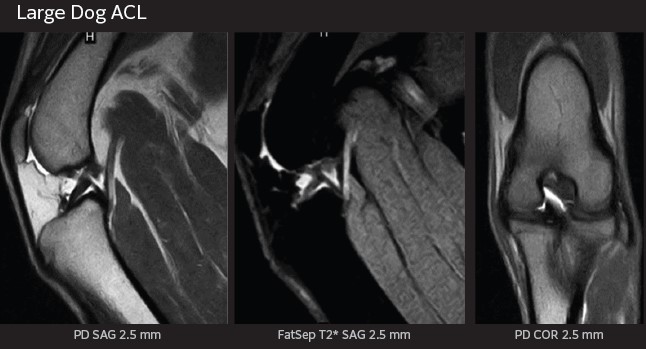

APERTO Lucent VET’s wide, laterally moving table and wide selection of high-sensitivity coils enable effective imaging across a broad range of animal sizes and body shapes. The open magnet design accommodates support equipment and in-place interventional procedures.

• RF FatSat suppresses fat signal, enhancing soft tissue and pathology visualization

• IP-RECON iterative reconstruction delivers exceptional image quality with faster scan times